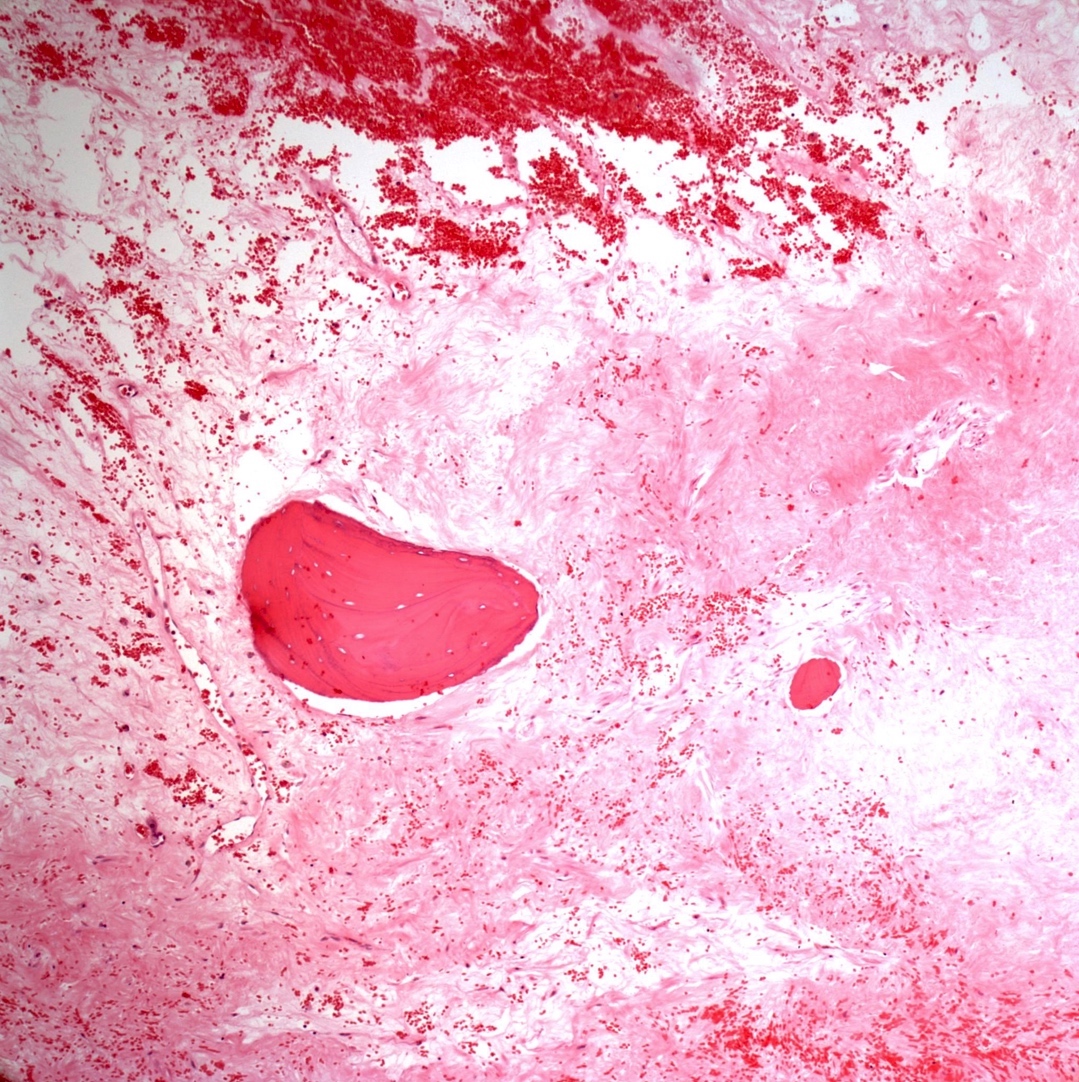

- Telangiectatic osteosarcoma: the tumor is multiloculated with large blood filled spaces; high grade malignant cells and neoplastic bone in septa (the imaging differential diagnosis is with aneurysmal bone cyst)

Microscopic (histologic) images

Contributed by Jesse Hart, D.O., Borislav A. Alexiev, M.D. and AFIP

A 12 year old girl has a 10.5 cm intramedullary mass in the distal femur, which was resected (see gross and microscopic images). High power views demonstrate bland spindle cells. Which of the following is most accurate regarding this tumor?

A. Most likely, genetic abnormality is amplification of the MDM2 gene. The tumor is a low grade central osteosarcoma.